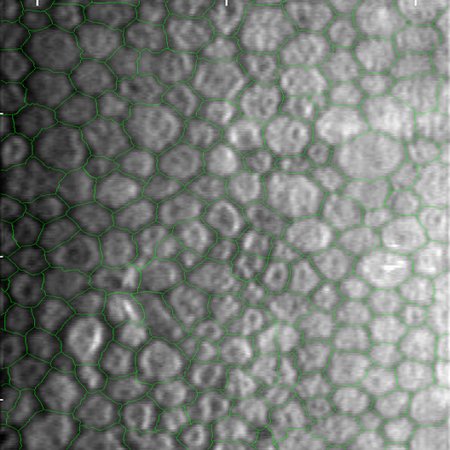

Usage: Perfect for generating synthetic ground truth data for medical image segmentation tasks (e.g., training U-Net models) or creating procedural biological textures.

Creating Paired Datasets: You can use this LoRA to generate a binary mask first, and then feed that mask into ControlNet to guide my model "Medical SEM Style: Corneal Cells".

Result: This workflow produces perfectly aligned (Image, Label) pairs, which are essential for training segmentation networks (like U-Net) without manual annotation.